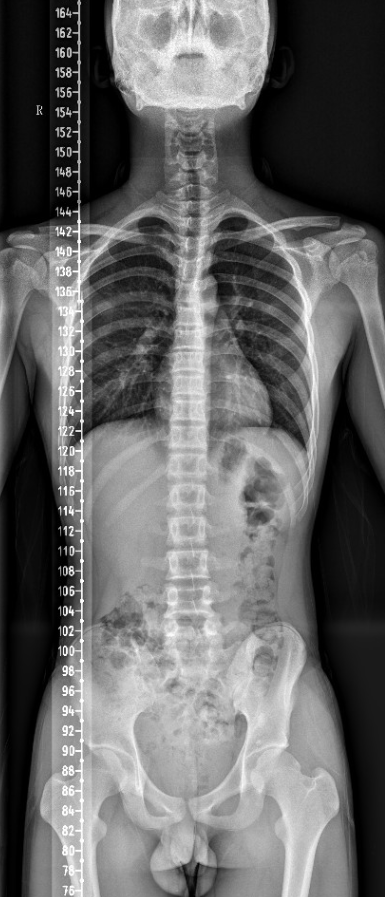

【影像】全脊柱X线示:胸曲过大,腰椎棘突偏左,髂骨右侧宽左侧窄,骨盆后倾。

腘绳肌及小腿三头肌挛缩,牵拉坐骨结节向下,骨盆后倾。患者腰椎棘突偏歪,椎体旋转,屈曲功能下降。患者坐位时骨盆后倾,当以屈腰代偿屈髋不足,因其屈腰受限,故以加大胸曲代偿,背部竖脊肌长期过度牵张而劳损,发为背痛。故操作时不治在上肌肉损伤(病之标),而疗在下之肌肉挛缩(病之本),不但效速,且能效久。